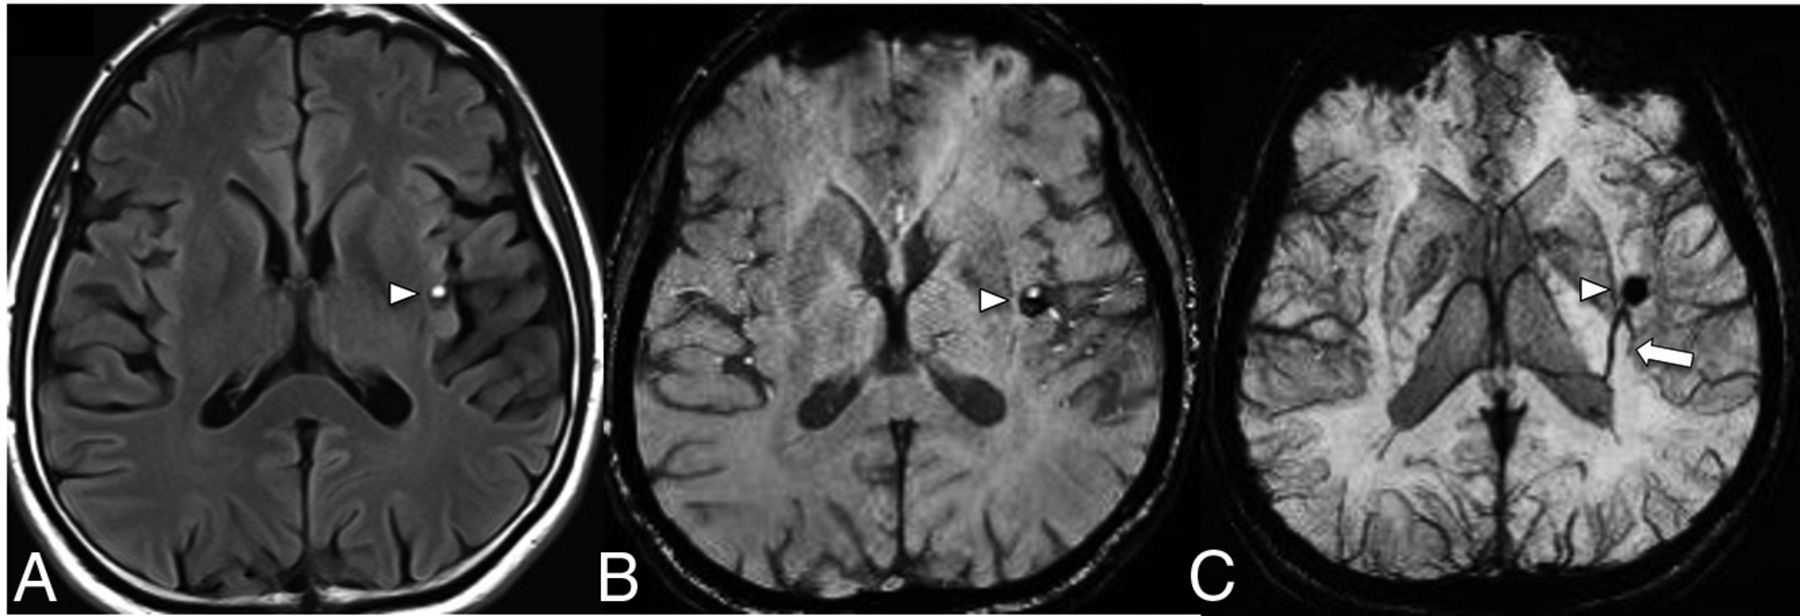

The collector vein of a DVA can rarely lead to a mechanical effect on adjacent structures. In the posterior fossa, collector veins near the root entry zone of cranial nerves can lead to neurovascular conflicts such as trigeminal neuralgia. The neurovascular decompression procedure requires more attention because the venous wall of the DVA collector vein is more delicate than an arterial vessel and has to be preserved. Rarely, the DVA collector vein can obstruct CSF flow at the cerebral aqueduct (Fig 10).31 Depending on the degree of obstruction and resultant hydrocephalus, there may be a need for CSF shunting or an endoscopic ventriculostomy CSF diversion procedure as a treatment.32

A midline midbrain DVA with the collection vein (arrow) obstructs the cerebral aqueduct leading to ventriculomegaly. SWI (A) shows the radially oriented medullary veins in the midbrain and an associated microbleed in the left anterior thalamus (arrowhead). T2-SPACE (B) and gadolinium-enhanced T1-weighted (C) images depict the location of a large collector vein obstructing the entrance into the cerebral aqueduct. Images courtesy of Dr Arjuna Somasundaram and Dr Christian Schwindack.